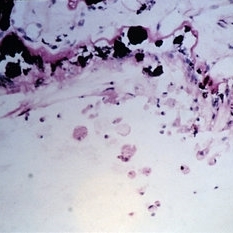

Slide 10-25

Feb 26 2019 by Lancaster Course in Ophthalmology

Phacolytic glaucoma. Histiocytes on the surface of the ciliary epithelium ( x 110). (Scheie Eye Institute, No. 3311.)

Condition/keywords: epithelium, phacolytic glaucoma